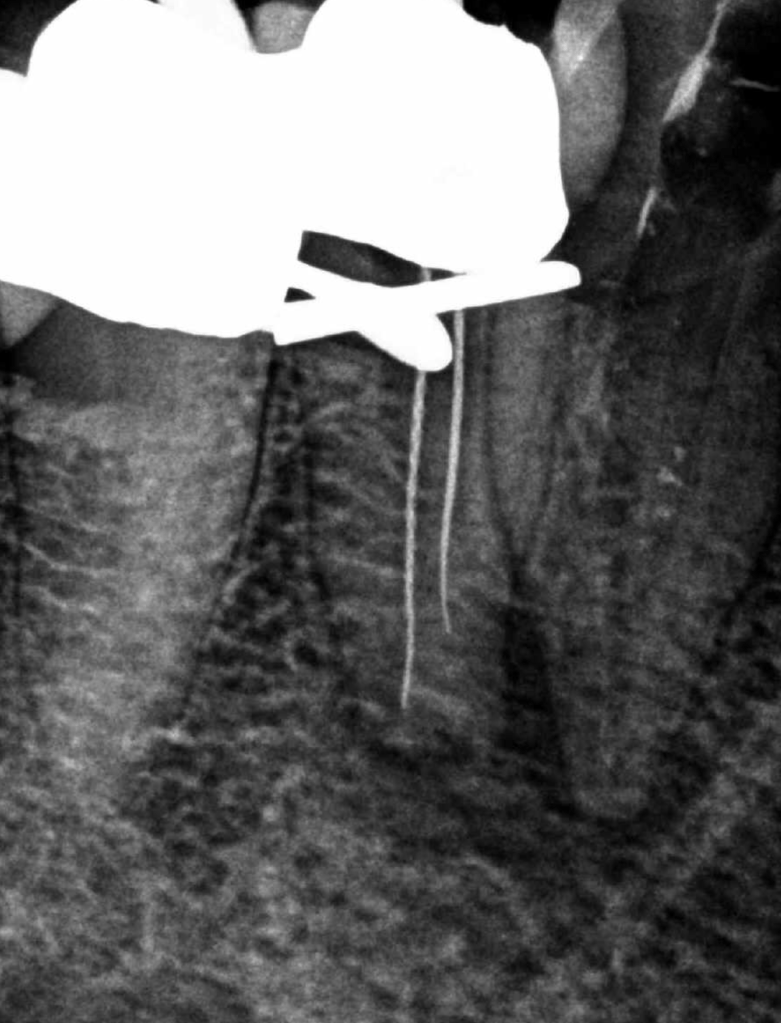

Molar inferior, conducto MC, Reeco prendo